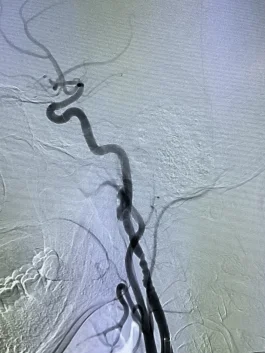

右图:颈动脉夹层

左图:开通后的血管

右图:取出的血栓